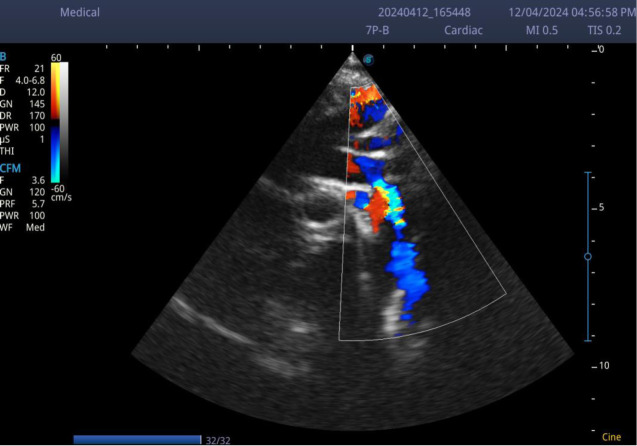

主动脉缩窄是一种梗阻性的先天性心脏缺陷,表现为上肢高血压。如果不及时治疗,主动脉缩窄可导致左心室功能障碍和脑血管病。由于其微妙的表现漏诊是常见的伴随并发症。这是一个病例报告,一个表面上健康的3岁男孩在轻微跌倒后陷入昏迷。他有上肢高血压,下肢脉搏几乎摸不到。脑部计算机断层扫描(CT)显示非外伤性出血性中风,超声心动图显示严重的左心室肥厚和主动脉严重缩窄。主动脉缩窄可表现为慢性上肢高血压患儿并发非外伤性出血性中风。幼儿常规血压测量可作为早期诊断的筛查工具。

Coarctation of the aorta is an obstructive form of congenital heart defects that presents with upper limb hypertension. If untreated, Coarctation of the aorta can lead to left ventricular dysfunction and cerebral vasculopathy. Missed diagnosis due to its subtle presentation is common with attendant complications. This is a case report of an apparently healthy 3-year-old boy who lapsed into a coma after a trivial fall. He had upper limb hypertension and the pulses in the lower limbs were barely palpable. Brain computed tomography (CT) revealed non-traumatic haemorrhagic stroke and echocardiography showed severe left ventricular hypertrophy and severe coarctation of the aorta. Coarctation of the aorta can manifest as chronic upper limb hypertension in children with complicated non-traumatic haemorrhagic stroke. Routine blood pressure measurement in young children can serve as a screening tool for early diagnosis of the condition.